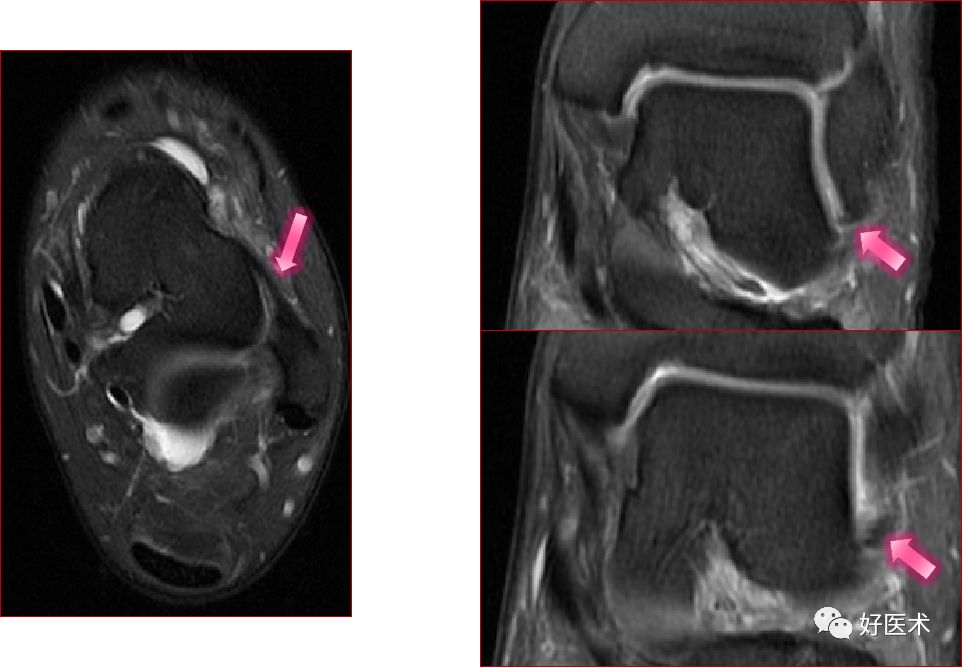

胫骨后肌肌腱撕裂